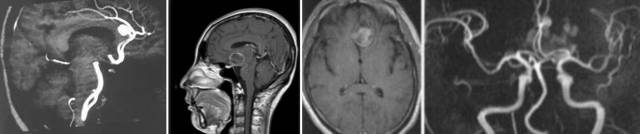

影像学检查–CT:

平扫—般为圆形、葫芦形或条形稍高密度影,动脉瘤壁有钙化时,CT易于显示。如动脉瘤破裂出血则表现为蛛网膜下腔出血,平扫是瘤体不易显示时,需要行CTA扫描。

CT增强—多数动脉瘤腔呈明显的均一强化圆形或不规则形,边缘清晰,有时增厚的动脉瘤壁亦发生强化,表现为在明显均一强化边缘有一轻度的强化环。

CTA—囊状动脉瘤表现为起自动脉的囊袋状突起,有蒂(瘤颈)与载瘤动脉相连,轮廓清晰;梭形动脉瘤表现为血管不规则迂曲扩张,无瘤颈。

影像学表现–MR:

MRI平扫:动脉瘤瘤腔内的血流呈“涡流”现象,在MRI上表现为无信号或低信号,但若动脉瘤腔内部分形成血栓,则信号改变就变得复杂化了。血栓中的正铁血红蛋白表现为高信号,若含有含铁血黄素则表现无或低信号;残留的瘤腔仍有流空效应,表现无或低信号;动脉瘤周边可有出血和水肿。

MRA:可以直接显示动脉瘤。

影像学表现–DSA:

DSA是诊断颅内动脉瘤最准确的方法,可清晰显示动脉瘤部位、大小、数量、形状。为了发现预料之外的动脉瘤,血管造影应包括所有部位的脑内血管。

造影应在出血后立刻进行,否则,出血2~3天后即发生血管痉挛,持续大约1周,此时造影,容易出现假阴性。